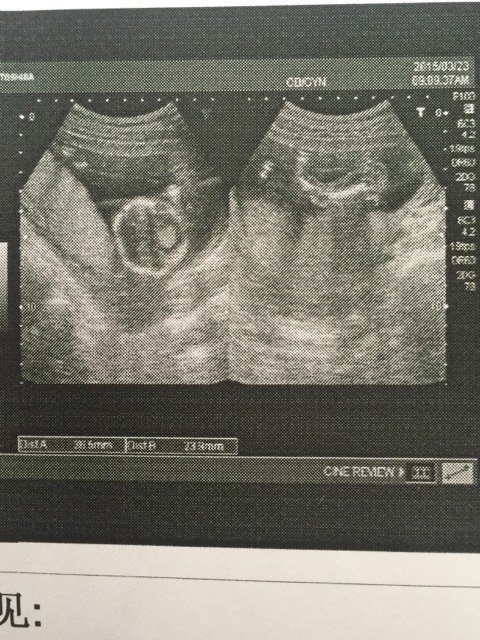

双顶径3.7 股骨长2.4 心率156 是男是女 双顶径3.7。 股骨长2.4。心率156。是男是女 点击展开 小小萝卜 2015-03-24 10:00 为您推荐: 其他回答 这个不准的 free蓝色的梦想 2015-03-24 14:12 看不出来的。做4维看的出来 小瑞恩麻麻 2015-03-24 10:58 正常情况下,单凭这些数据是无法判断出胎儿性别的,需要专业人员才能辨别出。 qq286550079 2015-03-24 10:25 女宝宝…… Ting婷系衰囡 2015-03-24 10:25 看不出来饿 爱涵仔 2015-03-24 10:08 加载更多 相关问题 怀孕14周彩超数据显示双顶径2 81mm胎心率156/分请问是男是女 孕3个半月双顶径32股骨长17 5羊水49心率156 孕39周b超检查双顶径8 8股骨长6 7羊水11 1胎心率156次每分正常吗